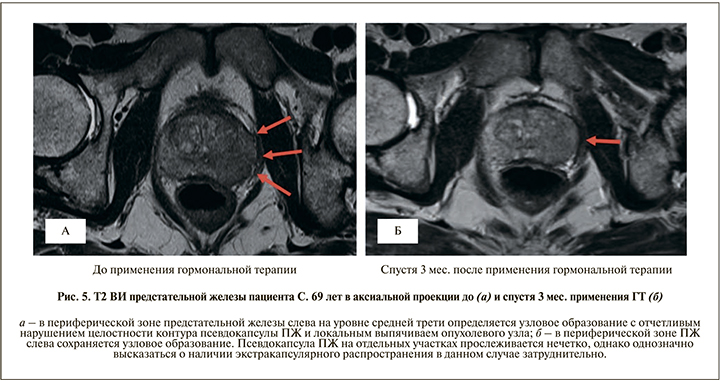

Другой значимой проблемой в оценке местной распространенности РПЖ является назначение ГТ, которая широко применяется при лечении больных РПЖ [11], до проведения мпМРТ. Ее действие основано прежде всего на подавлении секреции тестостерона, выработка которого провоцирует рост опухоли ПЖ. Гормональная терапия также приводит к уменьшению размеров ПЖ, что в свою очередь положительно сказывается на результатах хирургического лечения. Однако с уменьшением размеров ПЖ пропорционально уменьшается степень выраженности экстракапсулярного компонента РПЖ, что приводит к снижению точности интерпретации данных и в конечном итоге к недооценке местной распространенности опухоли по данным мпМРТ (рис. 5). Таким образом, для исключения диагностических ошибок при оценке местной распространенности опухолевого процесса предоперационную мпМРТ желательно выполнять пациентам до назначения ГТ.